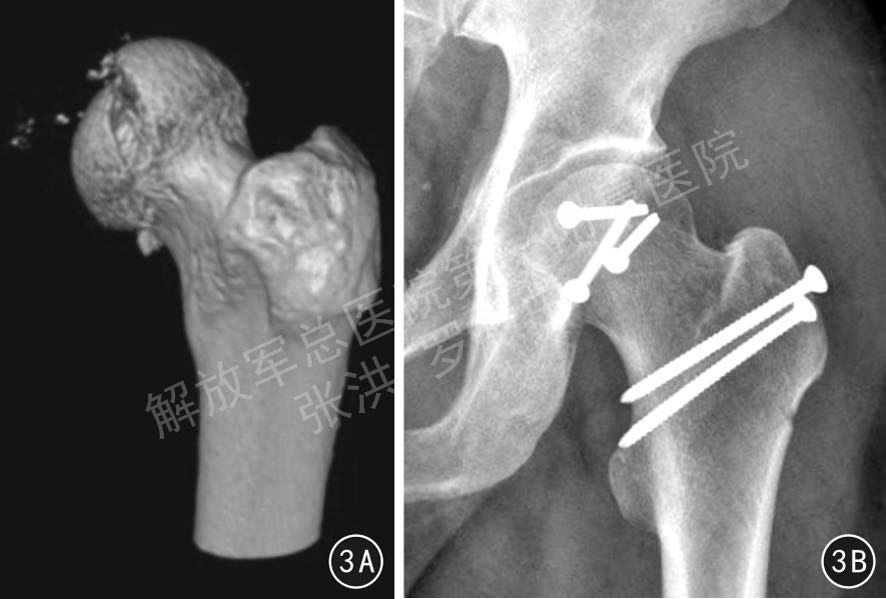

对于髋关节绒毛结节性滑膜炎、滑膜软骨瘤病、股骨头颈区骨囊肿/内生软骨瘤、髋臼底部骨囊肿/内生软骨瘤等良性病变,传统方法是经SP入路(Smith-Peterson approach)或后外侧入路切开关节,进行清理和处理。近年来也有采用关节镜技术处理、经股骨颈开窗技术处理、经髂骨/ 耻骨开窗处理等,方法不一,但均存在处理不准确、不彻底的问题,同时存在股骨头坏死、易复发、髋周软组织创伤等风险。SHD给这类病变的处理带来了极大的变革,可以在不损伤股骨头血液循环的前提下进行病灶的彻底清理、开窗、刮除、植骨、准确摘取病变组织等操作。见图4、5。

图4 患者男,37岁,左髋关节色素绒毛结节性滑膜炎,经髋关节外科脱位手术入路行病灶清除植骨手术,4A 术前髋关节冠状位MR图片,4B 清理植骨后左髋关节正位X线片

图5 患者女,14岁,右股骨颈骨囊肿,经髋关节外科脱位手术入路行病灶刮除植骨内固定手术,5A 术前骨盆正位X线片,5B 术前螺旋CT经股骨颈轴位显示右股骨颈骨囊肿位于股骨颈后半部,5C 冠状位螺旋CT重建显示右股骨颈骨囊肿侵蚀股骨颈直径50%以上,5D 刮除植骨内固定术后3个月右髋关节正、斜位X线片示,大转子截骨、股骨颈植骨已愈合,无股骨头坏死